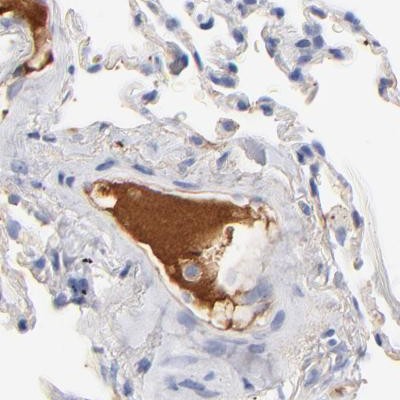

Immunohistochemical staining of human colon, kidney, lung and lymph node using Anti-APOH antibody HPA003732 (A) shows similar protein distribution across tissues to independent antibody HPA001654 (B).